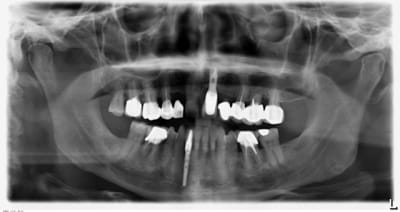

Présentation du cas : extraction de 26 , attente 2 mois cicatrisation, hauteur résiduelle estimé à 5 mm , mauvaise surprise après avoir oté le provisoire, très belle crète bien large mais invaginée en son centre.

Forage au milieu à 3mm + effraction du plancher ,manoeuvre de Walsava OK, bourrage au Gen Oss (0.5cc) , re Walsava, et implant IDCAM 10/5.2 bloqué au maximum .

oups , les photos de ce matin.

> oups , les photos de ce matin.

sur la radio post-op, l'espace entre l'implant et la pré-molaire, non comblé, ne causera pas de problème ?

J'aurais tenter un SA-3, pour comblé plus large et évité ce vide, qui est un ramasse bactérie dans le sinus...

pour céramik

peut être , mais je parie plutot sur une remontée générale du plancher dans ce secteur, vu la faible distance avec la prémolaire.

Tiens jette un coup d'oeil sur la partie mésial de cet implant sans comblement où 3 spires ont été englouties dans la cicatrisation osseuse

Cette histoire de poche est très intéressante et l'article de Moheng également.

Mais des panos de sinus lift par voie latérale fait par des confrères spécialisés où il y a un gros manque au niveau de la partie distale du pilier canin je peux t'en montrer quelques unes...